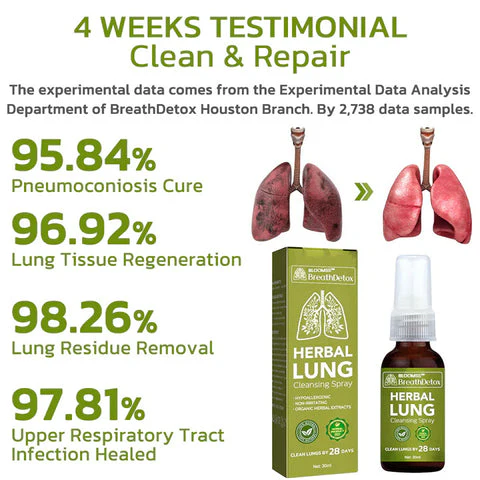

Clinical trials and surveys have yielded compelling evidence supporting the effectiveness of this medication in the treatment of chronic pharyngitis, pulmonary nodules, and pulmonary dysfunction. Furthermore, it has demonstrated notable efficacy in managing environmental allergies and asthma. Additionally, thorough verification has established the significant role of the spray in both treating and preventing the consequences of pulmonary inflammation. These findings contribute to the growing body of evidence highlighting the medication’s effectiveness across a range of respiratory conditions.